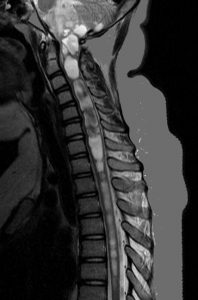

小脳虫部の毛様粘液性星細胞腫が第4脳室を閉塞して,閉塞性水頭症になっています。左の画像のように側脳室に水がたまってパンパンになっています。頭痛が生じて嘔吐しますが,ひどくなると意識障害となります。